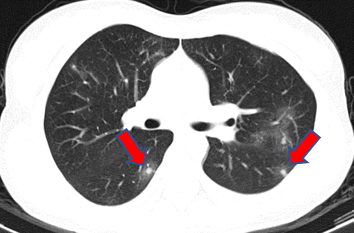

水痘-带状疱疹病毒

张奶奶退休后一直在家含饴弄孙。前段时间小家伙被幼儿园同学传染了水痘,发烧出痘折腾了好久,一家人都累坏了。而一波未平一波又起,张奶奶自己又开始咳嗽起来,眼看着咳了一周还不好,查了胸部CT发现双肺有多发小结节。医生建议张奶奶做个支气管镜检查,好明确肺结节性质。

支气管镜检查之后,医生安排把取到的标本做微生物基因检测,竟然检出了“水痘-带状疱疹病毒”。看到报告,不用医生解释张奶奶自己也明白了:在照顾小孙子的过程中她日夜不离,很可能就是在这个过程中吸入了病毒。所幸治疗简单,口服抗病毒药物之后,张奶奶双肺的结节都渐渐吸收了。